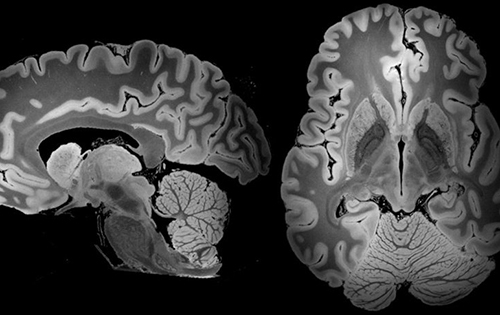

Продолжавшееся рекордные 4 дня МРТ-сканирование позволило ученым обрести детальные снимки мозга. На деле, это наиболее подробные МРТ-сканы мозга из всех, когда-либо полученных наукой. Они уже позволили выявить крошечные изменения в этом органе, которые могут стать очень ценными на пути более глубокого понимания таких состояний, как депрессия и кома. Естественно, что учёные проводили МРТ-сканирование мозга умершего человека, поскольку живой пациент не смог бы вынести 4 дня в МРТ сканере,да ещё из при условии абсолютной неподвижности. Кроме того, в организме живого человека осуществляется кровоток, который снижает точность данного сканирования.

Сообщается, что исследователи применили МРТ-сканер, который значительно превосходит по мощности использующееся в больницах оборудование. В результате, получены снимки мозга, на которых можно разглядеть участки площадью менее 0,1 мм. Ученые подчеркивают, что ранее не видели ничего подобного и с нетерпением готовятся применить полученные сканы для изучения здоровья мозга.

Общая продолжительность сканирования, проводившегося в Центральном госпитале Массачусетса в Бостоне, составила свыше 100 часов. Отметим, что обычное МРТ-сканирование живых пациентов продолжается от 15 до 90 минут. Исследователи надеются глубже разобраться с анатомией человеческого мозга, его здоровьем и болезнями. Сам мозг, который так долго сканировали, принадлежал умершей три года тому назад от пневмонии 58-летней женщине, он не имел никаких неврологических повреждений.